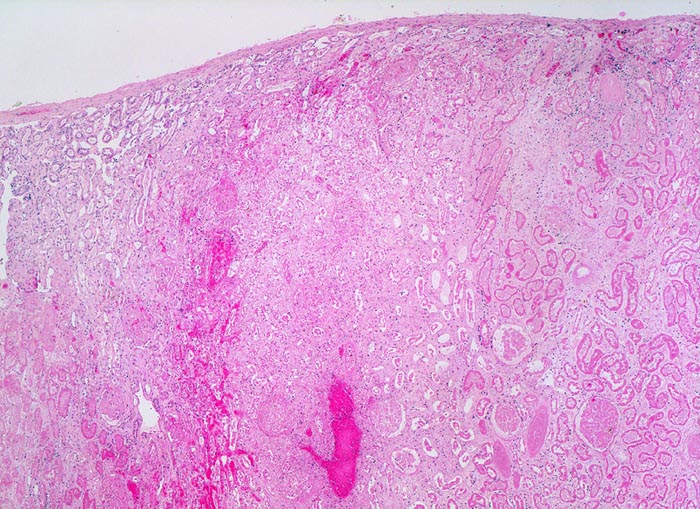

akuter Niereninfarkt

Im Infarktareal sind Tubuli und Glomerula noch schattenhaft erkennbar. Hämorrhagischer Randsaum zwischen Nekrose und vitalem Parenchym. Ein sehr schmaler Saum von vitalem Parenchym ist an der Rindenoberfläche dank Kollateralen aus der Nierenkapsel erhalten.

Chronisches Vorhofflimmern mit Morbus embolicus: anämische Infarkte verschiedenen Alters in beiden Nieren und in der Milz. Alte abgebaute Enzephalomalazie im Versorgungsbereich der Arteria cerebri media rechts.